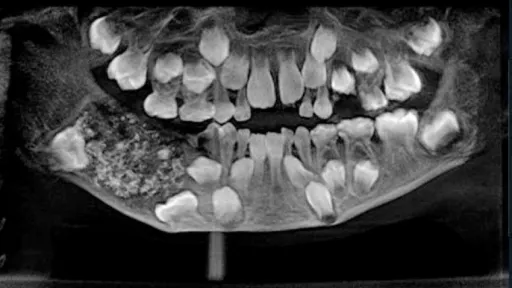

Un băiețel din India, care se plângea că îl doare gingia, a fost trimis la cabinetul medical al școlii unde învăța. La radiografie s-a văzut că băiețelul de 7 ani avea în gură nu 21 de dinți, așa cum ar fi fost normal la vârsta lui, ci 526.

Medicii le-au explicat părinților că e obligatoriu să se intervină de urgență, pentru a fi extrași dinții care nu ar fi trebuit să se afle acolo. În cele din urmă, după o oră și jumătate, medicii au reușit să extragă tot ce era în plus și s-au îngrozit.'Nu am văzut niciodată atâția dinți la un loc', a declarat unul dintre medicii care a luat parte la operație.'Arătau ca niște perle într-o stridie', a mai spus acesta. Medicii nu pot explica cum de s-a ajuns într-o astfel de situație.https://youtu.be/m56AwN2z5IMsursa